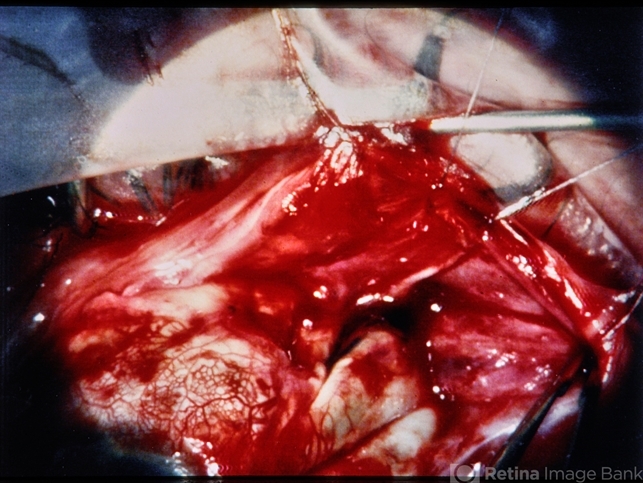

- Trauma Surgical View Long Scleral Laceration and Foreign Body

- trauma, scleral laceration, intraocular foreign body

- Further view of same eye, posterior laceration and large metallic foreign body